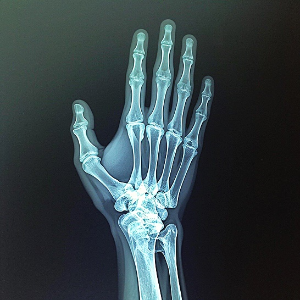

손가락 관절염은 질병 판단이 간단하지 않으며, 류마티스 관절염과 퇴행성 관절염과의 차별화가 요구됩니다. 의료진은 환자의 증상을 기반으로, 혈액 검사와 관절 X-레이를 통해 이를 진단하게 됩니다. 손가락 관절염을 치료하는 방법에는 여러 가지 요소가 포함될 수 있습니다. 다음은 주요 내용을 분류한 것입니다.